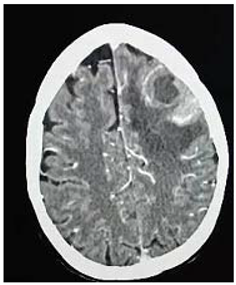

Preprints 114904 i001

Operation: Before the decision of surgery, we talked to the patient and her family clearly about the surgery complications and post operative outcome. Through left tempro- parito-occipital craniotomy, the tumor was macroscopically totally resects. It was sub cortical, well circumscribed ill define capsule, extended deeply to the underlining temporal horn of the lateral ventricle .Dural graft was taken from the tempralis fascia and was closed in water tide.

Patient was fully recovered from anesthesia and was taken to the ICU on nasal oxygen mask.

Histopathology

Brain tubeclomata ( extra pulmonary tuberculosis)

Patient was put on anti-tuberculosis according to the international protocol, and discharged free of headache, can see objects.